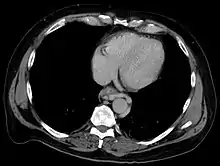

Axial CT showing esophageal varices in liver cirrhosis with portal hypertension